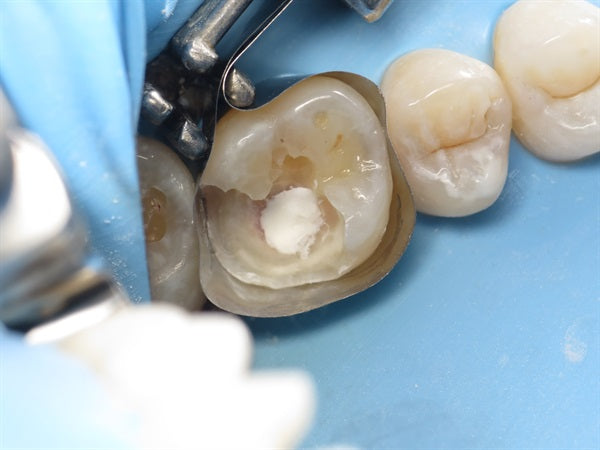

Direct composite onlay made simpler with occlusal stamping.

Posted on January 08 2019

Introduction: I have had great success with composite onlays, including teeth with root canals. Composite onlays are much more conservative than crowns. It is important to have a minimum of... Read More